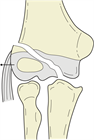

1. 受傷日に転位が2.0mm未満であった小児上腕骨外側顆骨折23例(2~ 11歳,男14女9)の後向き研究

1. 当院初診日の転位量が2.0mm以上であった6例は手術を行ったが、初診日までの外固定肢位は全例肘屈曲83°以下

1. 初診日の転位量が2.0mm未満であった17例は、前腕回内、肘屈曲96~120°で外固定し、全例骨癒合。可動域も良好。

まとめ:

転位量2mm未満の小児上腕骨外側顆骨折は、不適切な外固定が行われて転位することも多いが、前腕回内肘関節鋭角屈曲位での適切な外固定を行えば問題なく治癒することがほとんどである。